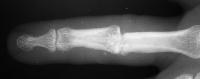

This young man had been treated for a rotating blade injury of the ring finger proximal interphalangeal joint. He had gross instability, pain and stiffness. These radiographs are before and after proximal interphalangeal joint reconstruction with the Avanta proximal interphalangeal joint surface replacement implant arthroplasty.

Oblique view: